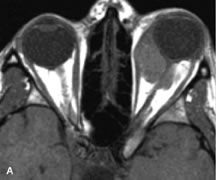

Fig. 21. A. T1-weighted MR scan demonstrates diffuse enlargement of both the superior rectus and levator palpebrae superioris muscles (single arrows). The involvement of the tendinous insertions and preseptal soft tissues (open arrows) as well as lack of involvement of other muscles helps differentiate this entity from thyroid-associated orbitopathy. B and C. Postcontrast fat-suppressed T1-weighted MR scans demonstrate extensive enhancement of the involved muscles as well as the preseptal (open arrows) and perinuscular tissues (double arrows).

Inflammatory conditions of the orbit, both idiopathic (inflammatory pseudotumor) and those of known causes, have been found to be hypointense to fat and isointense to muscle on Tl-weighted studies and isointense or slightly hyperintense to fat on T2-weighted images (Fig. 21).50,64,69 The more fibrous or sclerosing varieties have less signal intensity on T2-weighted images. Marked enhancement is seen in pseudotumor infiltrates after gadolinium administration.70 The same signal characteristics are demonstrated in patients with Tolosa-Hunt syndrome, with mass lesions seen in the cavernous sinuses and orbital apices.71